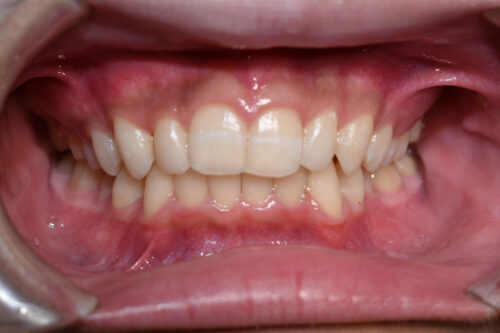

初診時年齢 17歳 男性

歯のでこぼこ (叢生)と

咬み合わせの深さ (過蓋咬合)を

気になさって

豊島区 巣鴨駅より ひとつ となり駅の

矯正歯科専門クリニック 大塚たまみ矯正歯科

へ いらっしゃいました。

歯のがたつき(叢生)が強く認められ

また下の歯が 全く見えず 過蓋咬合の状態でした。

ワイヤー矯正治療 8か月後です。